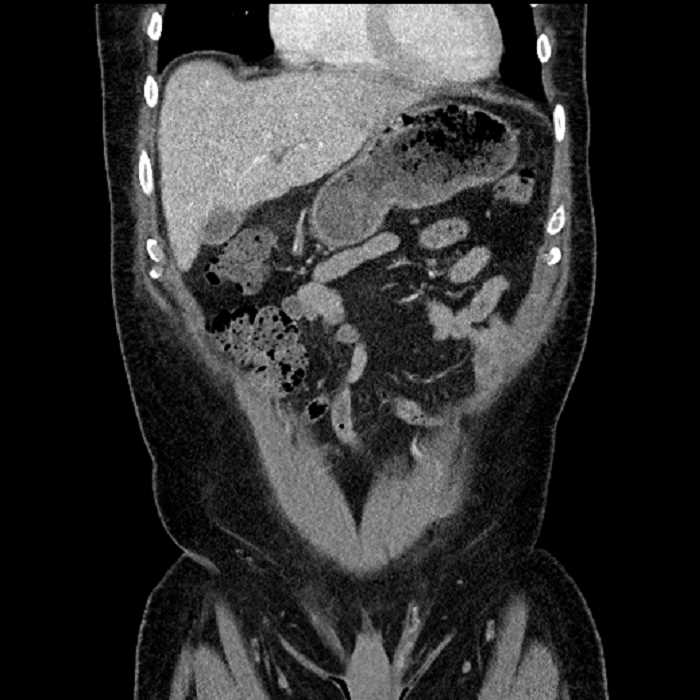

• Large fluid density structure in hepatic segments 7 and 8 measuring 10 x 7 x 7 cm with internal septation and circumferential ill-defined low density compatible with edema

• Peripherally enhancing subcapsular collections along the anterior margin of the left hepatic lobe measuring 3 x 1 cm and 2 x 1 cm

• Clearly marginated fluid density structure in segment 7 and several other scattered tiny hypodensities, which likely represent cysts

• Mild mural thickening of a segment of the sigmoid colon with adjacent fat stranding and a 1.5 cm fluid and gas collection along the tip of an inflamed diverticulum

• Loss of the normal fat plane between this collection and adjacent loops of small bowel, which demonstrate mural thickening

Acute sigmoid diverticulitis complicated by a small contained perforation and a large abscess in the right hepatic lobe. Additional small subcapsular abscesses along the anterior margin of the left hepatic lobe.

Additionally, loss of the normal fat plane between the peridiverticular collection and adjacent thickened loops of small bowel raises the potential for an enterocolonic fistula.